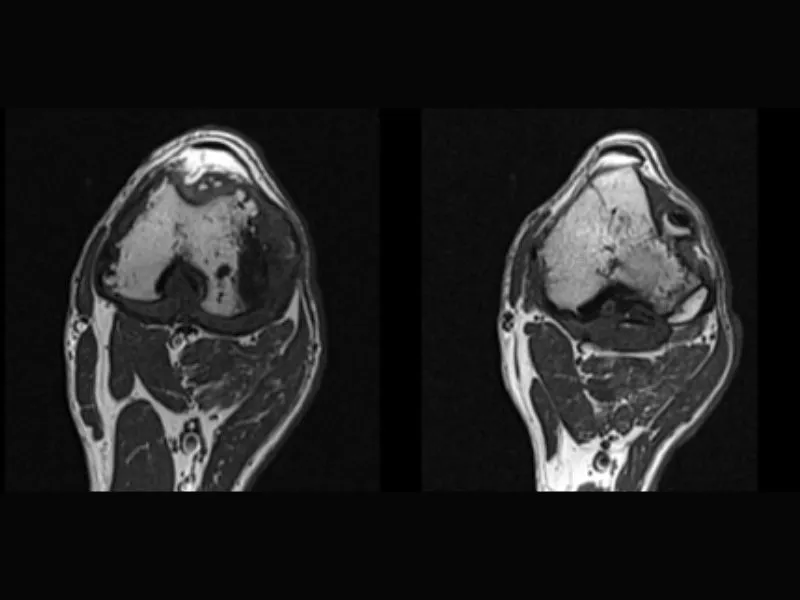

Supreme vet-mr – Arthritis of the canine stifle joint, Transverse T1W slices